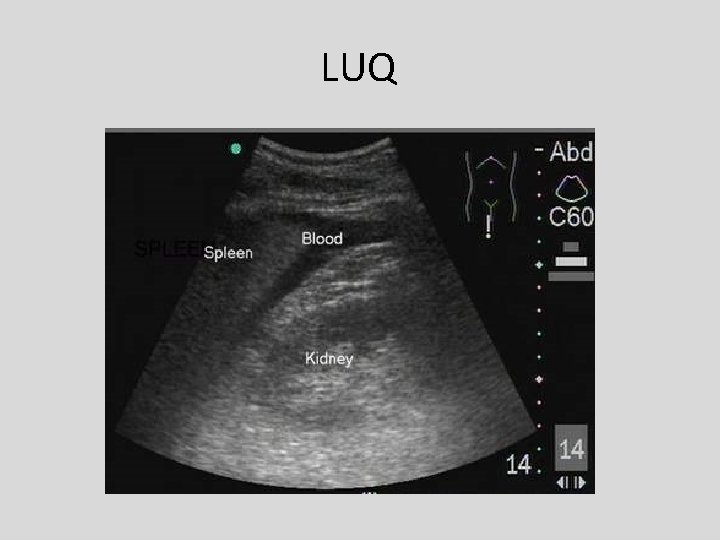

Left Upper Quadrant Window • Transducer positioned in left posterior axillary line with beam in coronal plane.

LUQ Window

LUQ